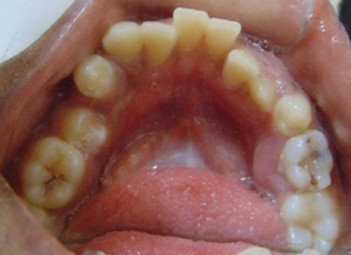

Before

After

Image 1

Image 2

Image 3

Abhinav Jain, 24Y, Duration - 8Months